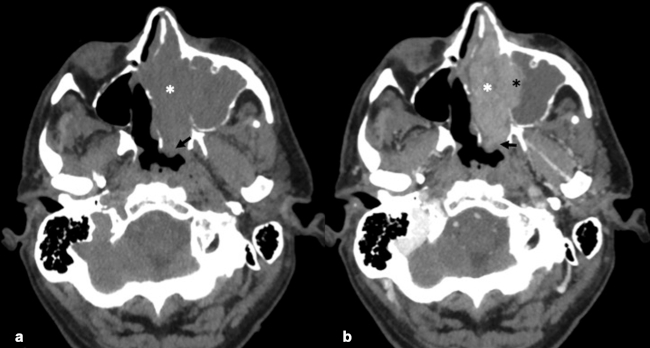

La TC de corte fino (espesor de corte de 1 mm) con reconstrucciones en plano coronal y sagital, es la mejor prueba de imagen inicial para el estudio del NBO. En la TC, aparece como una masa homogénea de tejido blando en la bóveda nasal con realce moderado y uniforme (►Figs.1y2). Se pueden encontrar calcificaciones punteadas dispersas (►Figs.2,3,4,5a,6).50 El valor principal de la TC es una mejor definición de la afectación ósea en comparación con la RM. La TC ayuda a evaluar la erosión ósea de la placa cribiforme, la fóvea etmoidal y la lámina papirácea (►Figs.1,2,3,4,5a,8). Sin embargo, la remodelación ósea sin erosión puede presentarse en algunos casos debido a su patrón de crecimiento indolente.3,35,49 Los estudios de TC generalmente revelan un patrón lítico y muy raramente hiperostosis dominante que simula displasia fibrosa.51 La TC también es útil para evaluar la presencia de metástasis regionales en cuello y a distancia.52,53